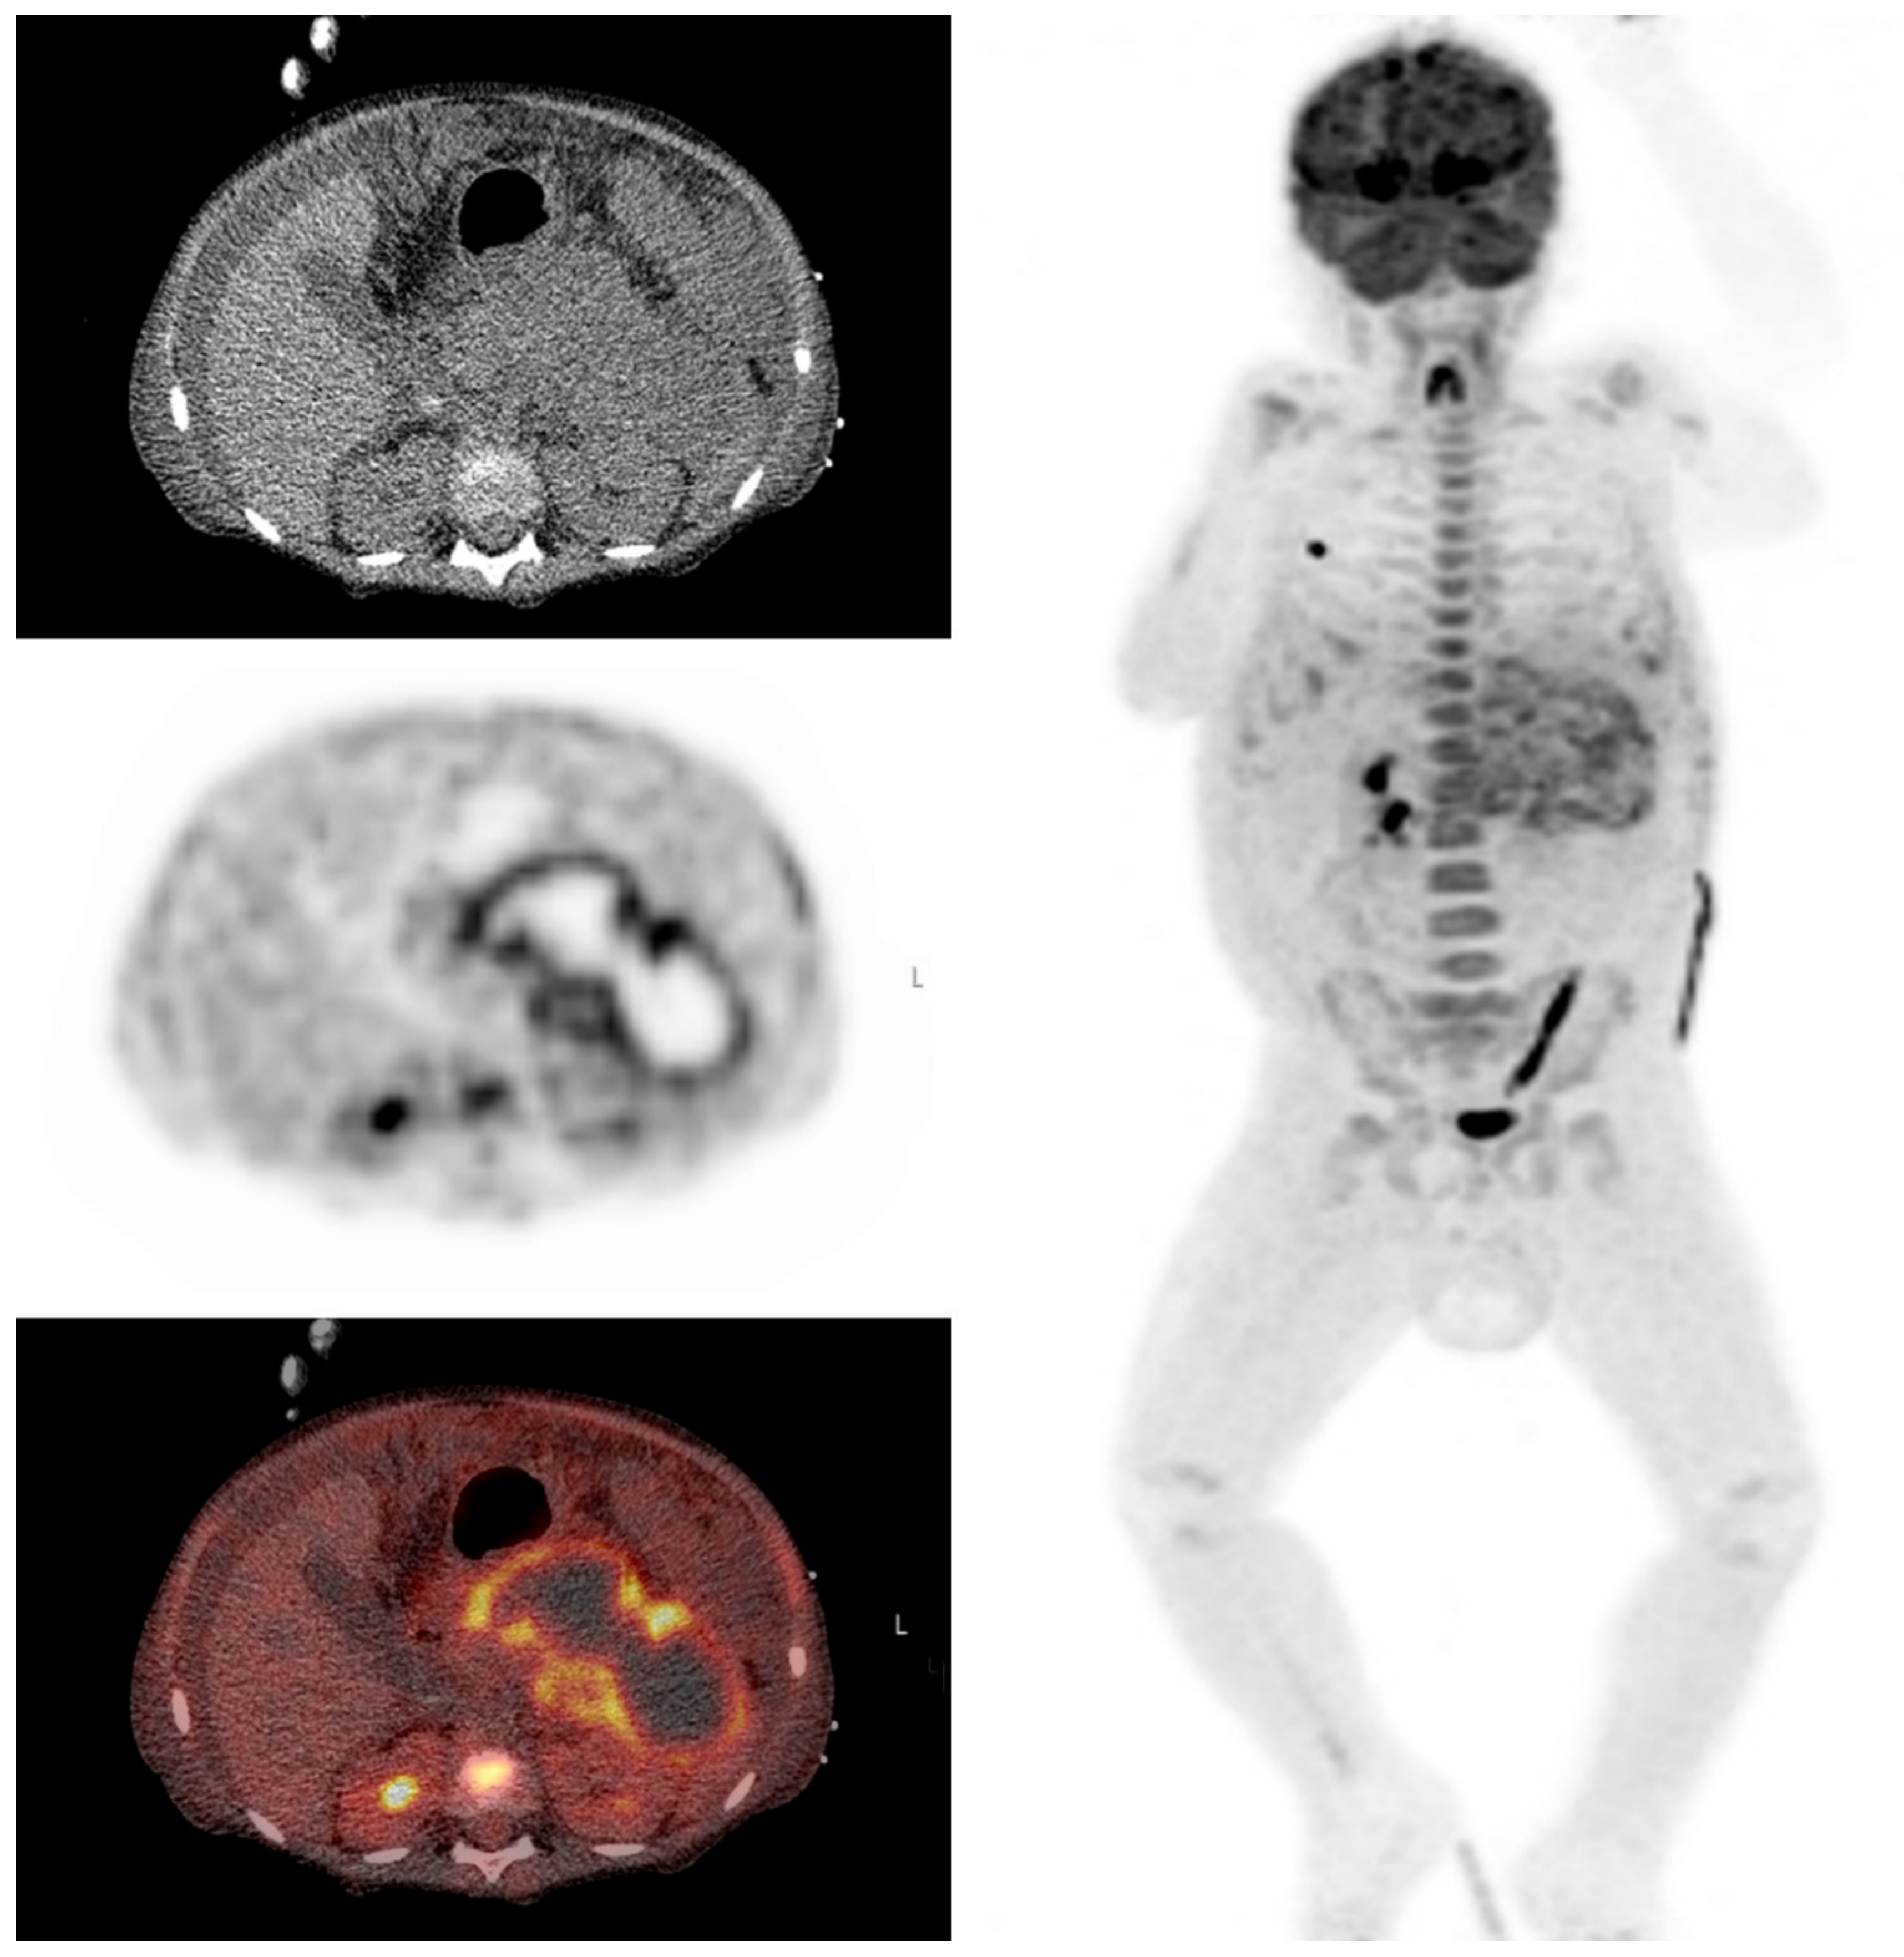

A 5-year-old boy with a history of nephrotic syndrome was admitted with fever, abdominal pain, nausea and a painful left leg. MRI of the leg did not show signs of osteomyelitis. CRP was 250 mg/L and pancreatic enzymes were elevated, suggesting pancreatitis. Antibiotics were started, but the fever persisted and his abdominal pain increased. An abdominal MRI was performed which showed signs of pancreatitis without cyst formation. A week later when symptoms were still persisting, FDG-PET/CT was performed, mainly to exclude other causes. FDG-PET/CT showed increased uptake in the periphery of an irregular hypodensity of 12 × 4 cm in the pancreas area, suggestive for an infected pancreatic pseudocyst. A transgastric drainage of the pseudocyst was performed and a stent was placed (Figure 7).

Figure 7.

Clinical example 3. This scan shows an irregular hypodense lesion in the pancreatic region on low-dose CT and a photopenic area with hot rim on FDG-PET.